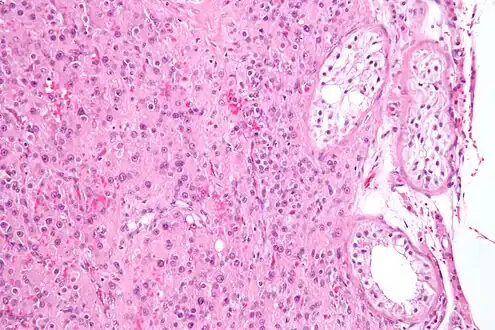

| Histopathology of a Leydig cell tumor, high magnification, H&E stain, showing typical features.[1] | |

A conclusive diagnosis is made via histology, as part of a pathology report made during or after surgery. Reinke crystals are classically found in these tumours and help confirm the diagnosis, although they are seen in less than half of all Leydig cell tumours. Immunohistochemical markers of Leydig cell tumours include inhibin-alpha, calretinin, and melan-A.[6]